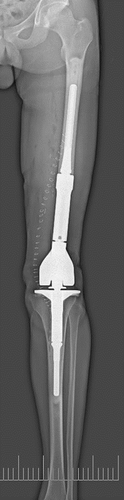

SLOT – рентгенография костей - способ получения на одном снимке протяженного объекта (позвоночного столба или конечности) целиком, в натуральную величину, без проекционных искажений. Применяется для измерений в ортопедии и при протезировании